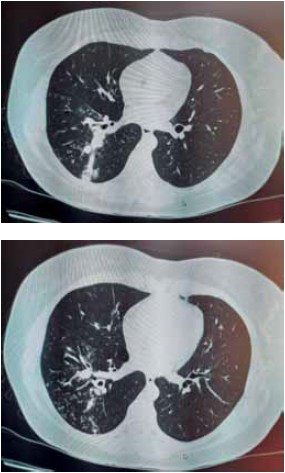

Paciente mulher, 34 anos, chega ao ambulatório com queixa de tosse produtiva, secreção mucosa, há 3 meses, sem outras queixas. Não apresenta alterações no exame físico. Solicitada tomografia computadorizada de tórax apresentada nas imagens a seguir.

Após a confirmação da etiologia do quadro pulmonar deve ser solicitada sorologia para infecção pelo

Assinale a alternativa correta.